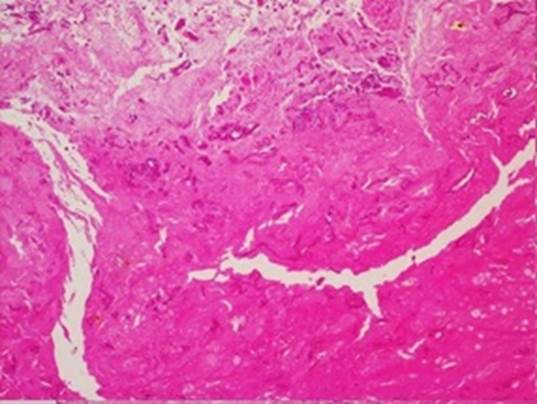

Figura 2 Tejido con extensa necrosis coagulativa e hifas anchas con pared delgada. Tinción con hematoxilina - eosina. Microfotografía a 4 x.

Figura 3 Tejido con extensa necrosis coagulativa e hifas anchas con pared delgada. Tinción con hematoxilina - eosina. Microfotografía a 10 x.